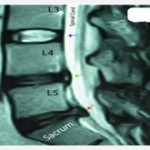

Inter Vertebral Prolapse Disc bears 20-33 % of entire weight of vertebral column has two parts :-

- Nucleus pulposus – It is a mucoprotein gel containing various mucopolysaccharids has water content 70-90%. Its function is to resist and redistribute compressive forces within the spine.

- Annulus fibrosis – It is a fibro cartilage with bundles of collagen fibers (lamina) in a crisscross pattern. Its function is to withstand high bending and torsional load.